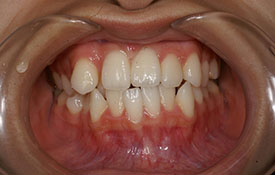

| プロフィール | 42歳 女性 |

| 所見 | 他院で行われた矯正歯科治療後の後戻りに悩まれて来院されました。 アイライナーの装着は、1日平均20時間ほどでした。 |